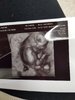

Moje malenstwo rozwija sie ksiazkowo jak powiedzial Doktor ;)

• 20190508_173136.jpg

1,6 MB · Wyświetleń: 121